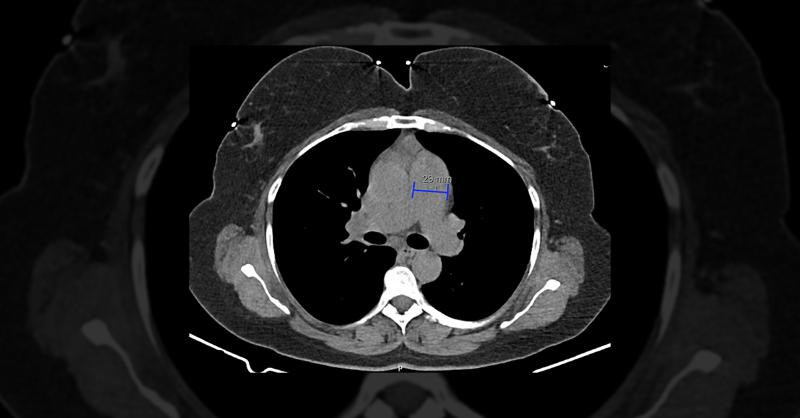

A 33-year-old woman, diagnosed with Graves' disease and treated for six months with methimazole and propranolol, presented with worsening exertional dyspnea, orthopnea, and fatigue. Her physical examination revealed no distress at rest, normal skin color, adequate hydration, and oxygen saturation of 98%. Jugular venous distension was noted, along w